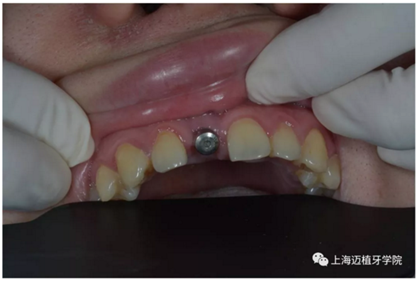

戴牙前口內(nèi)照片:

去除愈合基臺:

口內(nèi)個性化基臺: